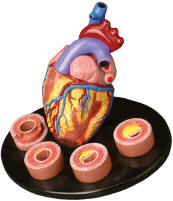

| Human Body Circulatory System -

bulk of the pages are on the Human Heart. The Starter Hearts vary

considerably, ranging from simple ones suitable for elementary education

to more advanced models. The pages that follow portray

increasingly detailed models, including many suitable for advanced

medical school education. These are suitable for internal medicine

and the study of cardiovascular diseases.